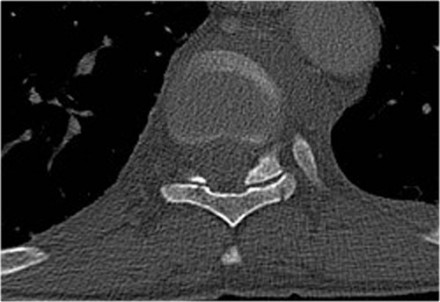

Case 6

Look at the images.

How would you describe the morphology and the PLC?

Then scroll to the next images.

The findings are:

- Morphology: Distraction - 4 points

- PLC: always torn in posterior distraction - 3 points

- TLICS based on imaging: 7 points

The key point in this case is that you should not describe this morphology as burst - 2 points.

The horizontal fractures on the posterior side and the increased

interspinous distance indicate distraction, which means a higher score

for morphology.

Always go for the highest possible score in TLICS.